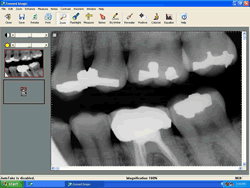

Computerized Digital Radiography

Our office was one of the first to introduce this technology to our patients in 1997.., . Before Schick, we placed each film in your mouth,one by one, exposed the film with the X-ray tube for about 1/3 second, removed it, then photochemically developed the film, waiting at least several minutes to view a roughly 1" square image on a light box. Magnification and viewing films was not easy, and duplication required exposing more film and yielded poor results. Films occasionally got lost or misfiled.

Today a Schick CDR sensor (it's similiar to the CCD element of a camcorder) wired to a PC with special software is placed in the mouth, exposed for 1/15 th of a second (that's right, 80 % radiation reduction to the patient) and the image appears in about a second on a 19 " computer monitor.

With Schick CDR, both the doctor and patient can clearly see the pictures which provides for better diagnosis and understanding.

Instant viewing, magnification, and unlimited duplication are possible and contrast and brightness can be adjusted after the picture is made.